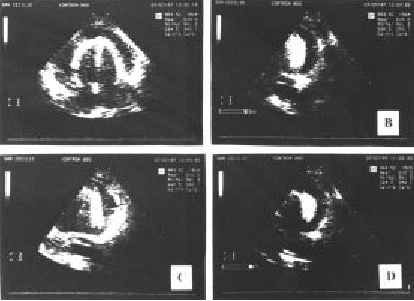

Figura 6.—Pericardiocentesis percutánea subxifoidea con control ecocardiográfico. Punción pericárdica para colocación de un catéter de drenaje (técnica de Seldinger modificada) guiada mediante ecocardiografía 2-D en un caso de taponamiento cardiaco. A: Imagen 4 cámaras con derrame pericárdico importante. B: Imagen mostrando la entrada en saco pericárdico de la aguja de punción. C: Imagen mostrando la introducción de la guía metálica a través de la aguja metálica. D: Imagen mostrando el introductor correctamente situado dentro del saco pericárdico. Una vez confirmada la situación del introductor dentro del saco pericárdico se pasará el catéter de drenaje.